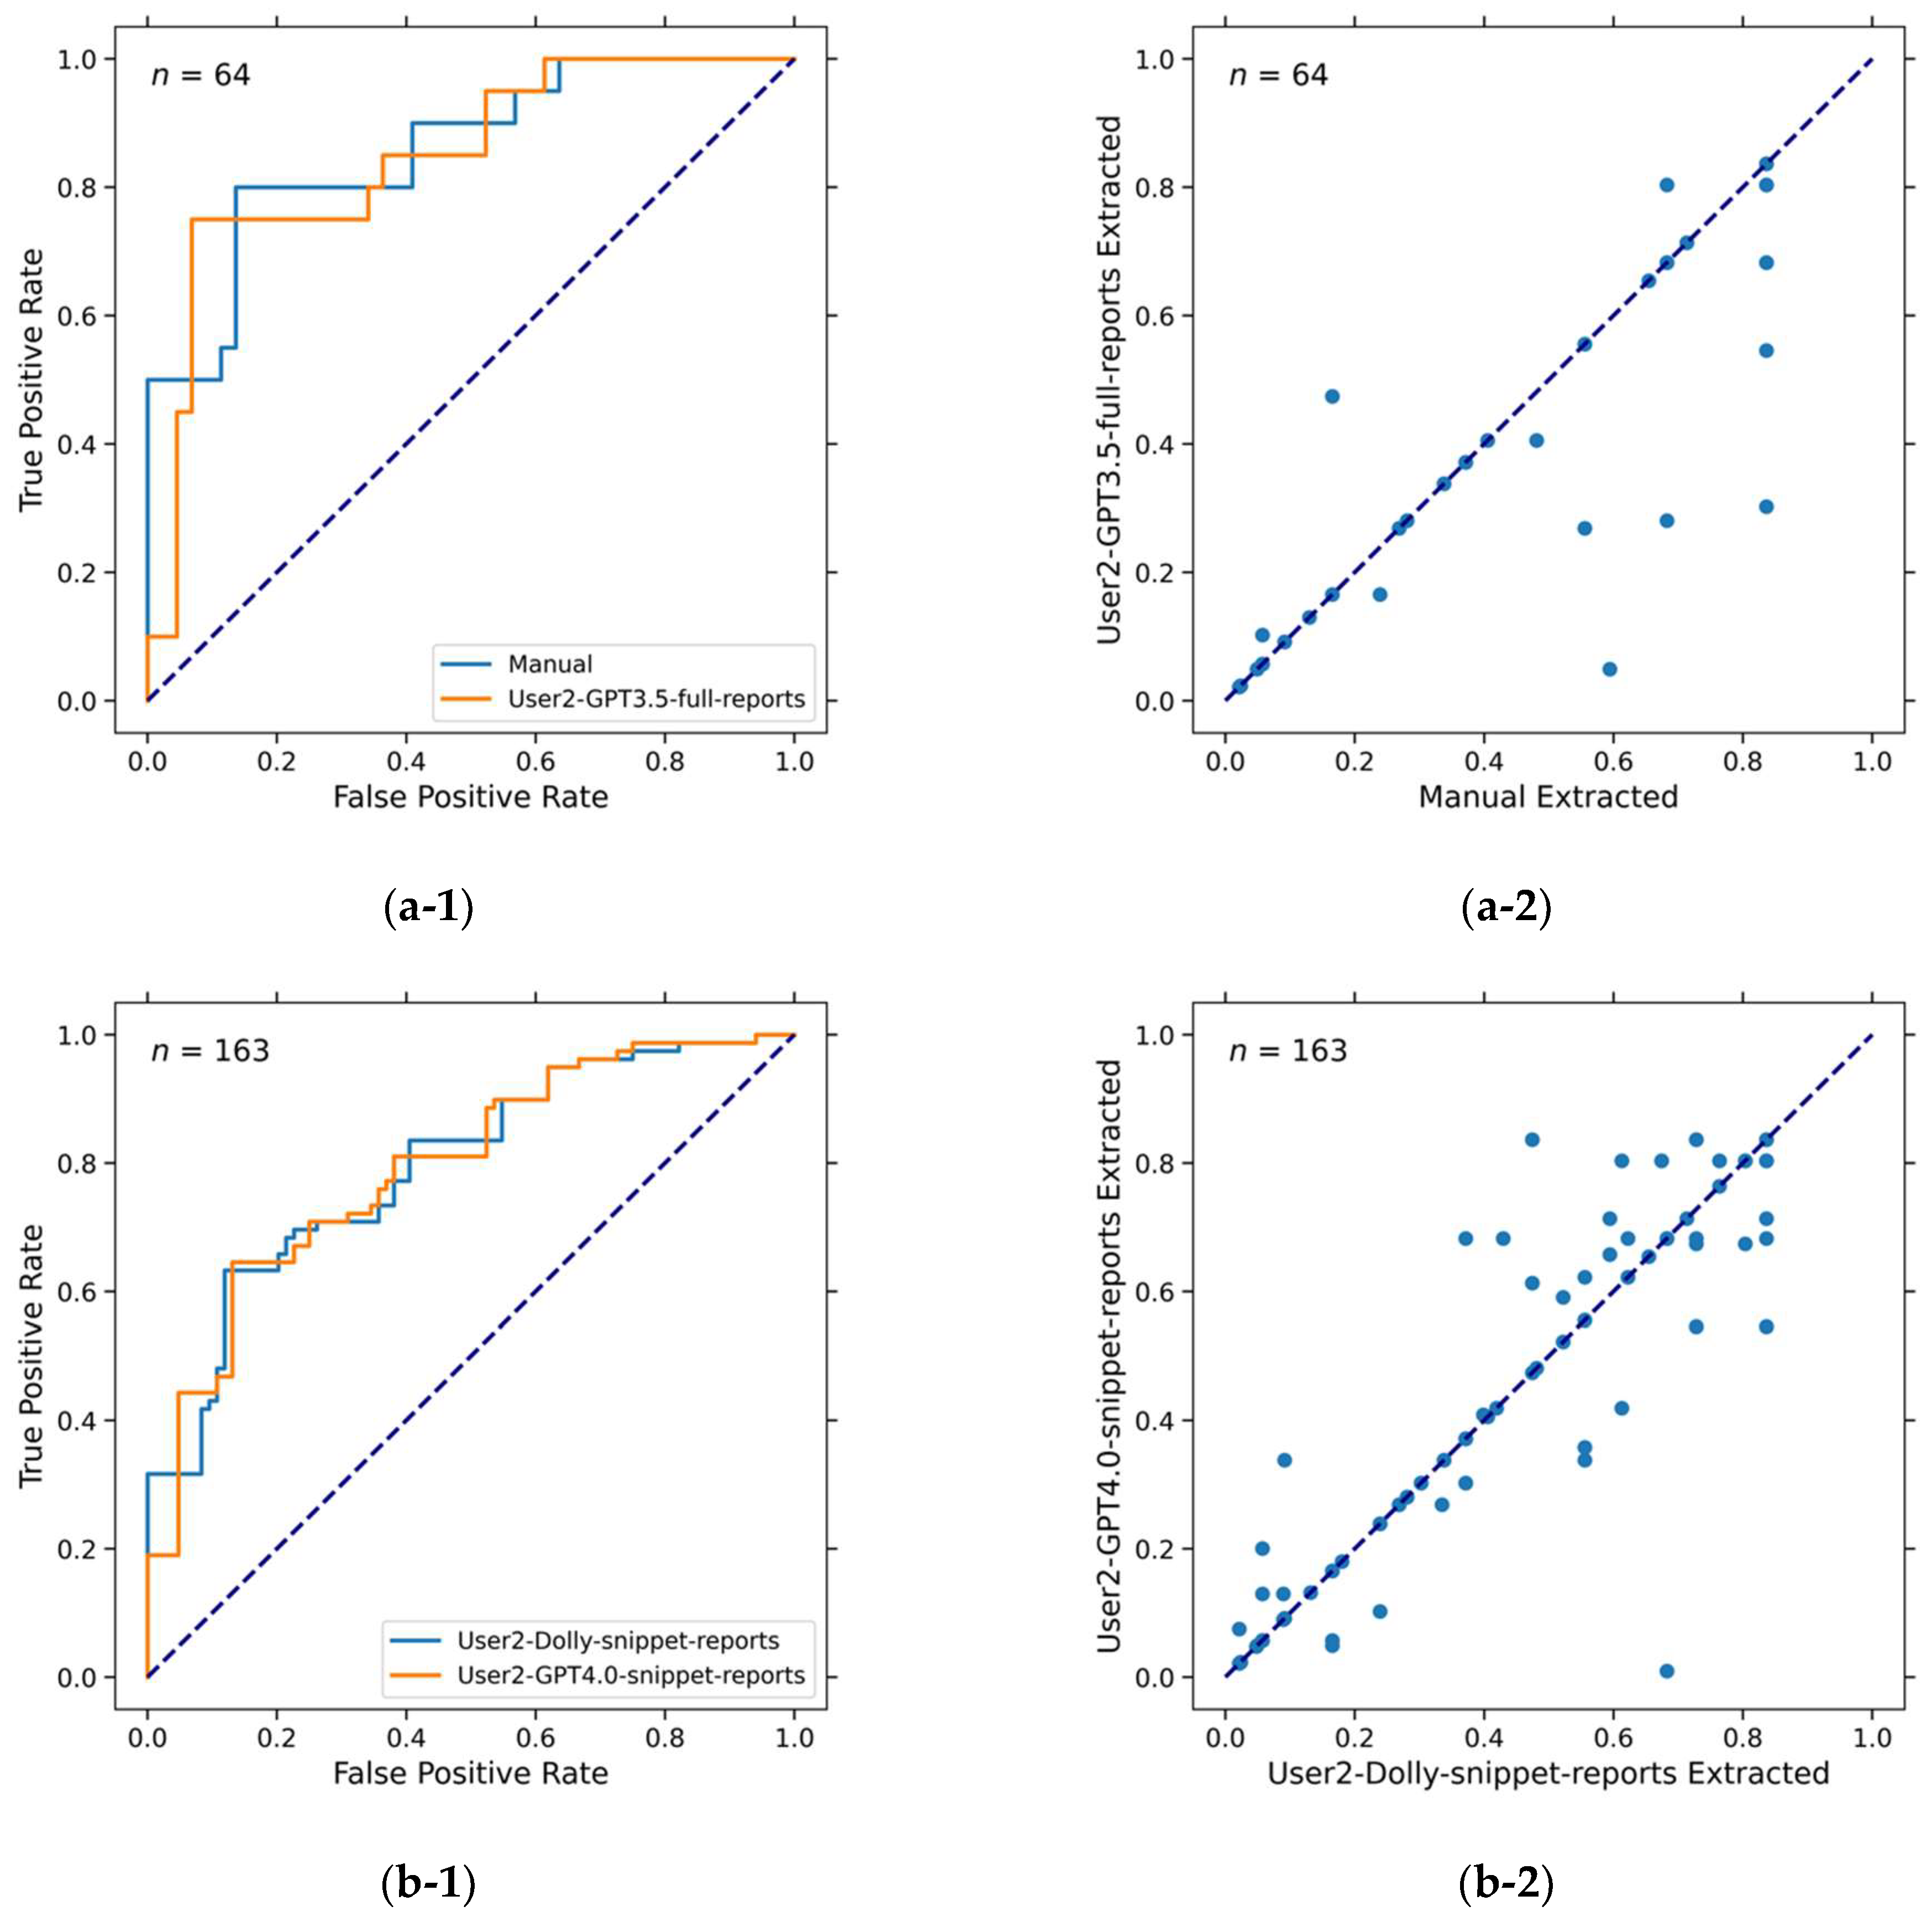

3.2. LLM Accuracy in Extracting Information

3.3. Five-Year Survival Prediction